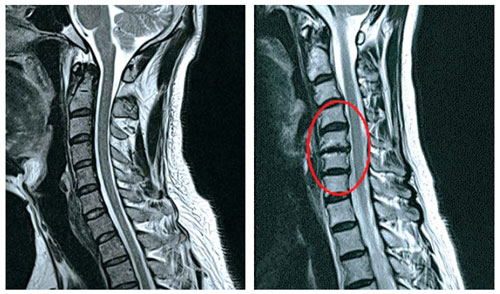

목디스크는 목 쪽 척추인 경추와 경추 사이에 위치한 추간판 사이로 내부의 수핵이 빠져나와서 신경근 또는 척수를 누르는 질환이며 목디스크의 정확한 명칭은 경추 추간판 탈출증이라고 합니다. 잦은 휴대폰 사용과 함께 업무를 볼 때 자연스럽게 구부정한 자세로 앉아 있다 보니 이로 인해 목디스크 증상까지 동반되는 경우가 많다고 합니다. 목디스크는 오랜 시간 축척된 경추 관절 및 디스크의 퇴행성 변화가 원인입니다.

목디스크를 치료하기 위해서는 무엇보다도 전문 병원에서의 현재 상태에 대한 정확한 진단이 필요합니다. 위에서 설명드렸다시피 본인이 어떤 원인으로 인한 목디스크 증상을 겪고 있는지에 대해서도 확인이 필요하며, 나아가 현재 디스크가 경추 사이에서 탈출되면서 어느 정도로 신경 부위를 압박하고 있는지 그 수위에 대한 확인도 매우 중요합니다.

하지만 비수술적 치료를 통해서 증상이 개선되지 않거나 혹은 목디스크 진행 단계가 심각하게 진행되어 있는 경우에는 곧바로 수술을 통하여 치료가 진행됩니다. 연성 디스크일 경우에는 후방접근법, 경성 디스크일 경우에는 전방 접근법으로 수술이 진행되며 이 두 방법 모두 경추부 디스크를 확인하기 위하여 목 부분 절개를 해야 하므로 전신마취를 해야 한다는 단점이 있습니다. 따라서 최근에는 전신마취 없이 목 부위를 약 1cm 정도만 절개하여 진행하는 내시경 미세 감압 수술 기술이 개발되어 수술 과정에 의한 사고 예방과 함께 환자의 수술 후 빠른 회복도 가능하다고 합니다.